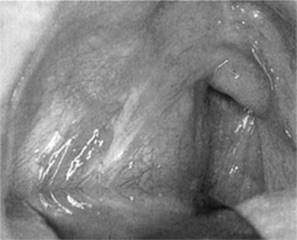

A quinsy (Fig 2.15) is a peritonsillar collection of pus, which is one of the most common complications of bacterial tonsillitis. It is managed through recognition and drainage.

Figure 2.15 Quinsy

From Dhillon & East, 2006